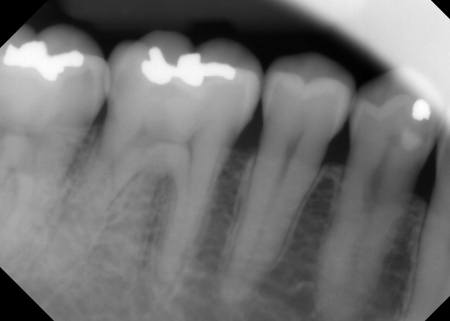

④上下左右の奥歯には、銀合金の古い詰め物「アマルガム」が装着されていました。今回は保険診療の範囲内で、CRと金属の詰め物「インレー」による修復を行い、全体的な噛み合わせと審美性を改善します。

最後に、古いアマルガムを除去した部分は保険診療の範囲で治療を行い、見た目や噛み合わせなどに問題がないことを確認して、治療を終了しています。